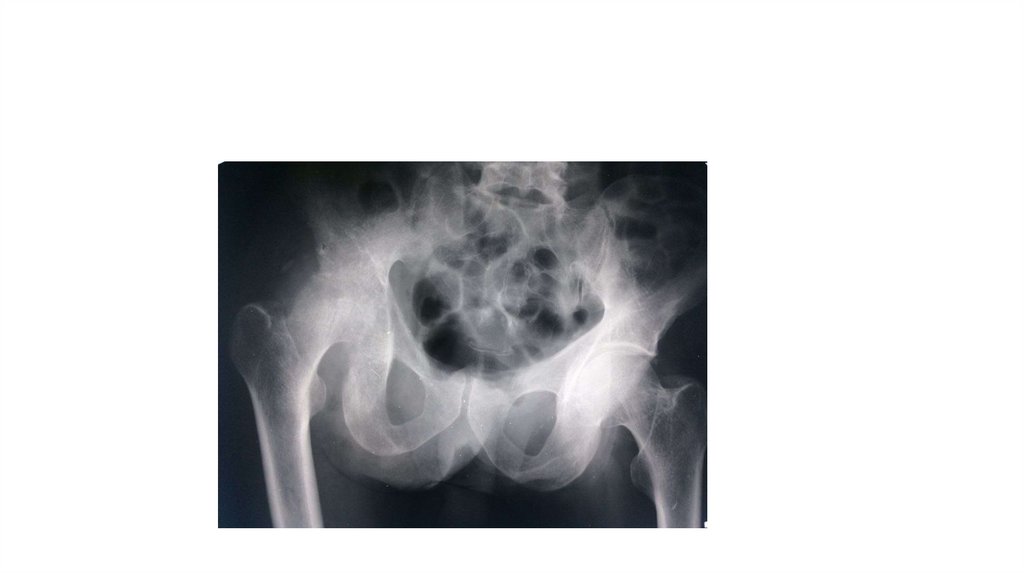

Воспалительные заболевания опорнодвигательного аппарата

«Воспалительные

заболевания опорнодвигательного аппарата»